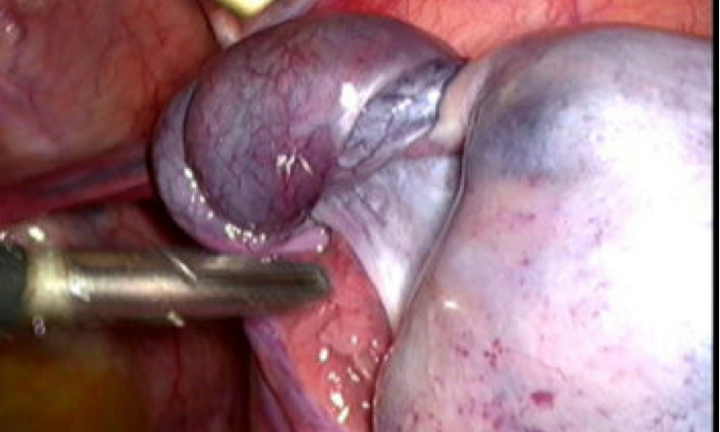

Cấp cứu tưởng đau ruột thừa, ai ngờ bé gái 10 tuổi bị u buồng trứng xoắn

Bé gái 10 tuổi ở Bình Dương được người nhà cho nhập viện trong tình trạng đột ngột đau hạ vị, nôn ói, không sốt.